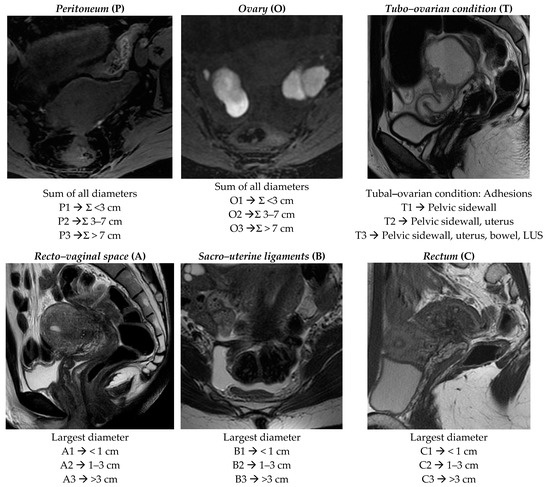

| SITE | Kappa | Z |

|---|---|---|

| Peritoneum (P) | 0.8912 | 17.28 |

| Ovary (O) | 0.8153 | 17.20 |

| Tubo–ovarian condition (T) | 0.5455 | 10.63 |

| Recto–vaginal space (A) | 0.7645 | 12.50 |

| Sacro–uterine/cardinal ligaments (B) | 0.7402 | 15.70 |

| Rectum (C) | 0.7932 | 15.91 |

| Extragenital deep endometriosis (F) | 0.6349 | 12.48 |